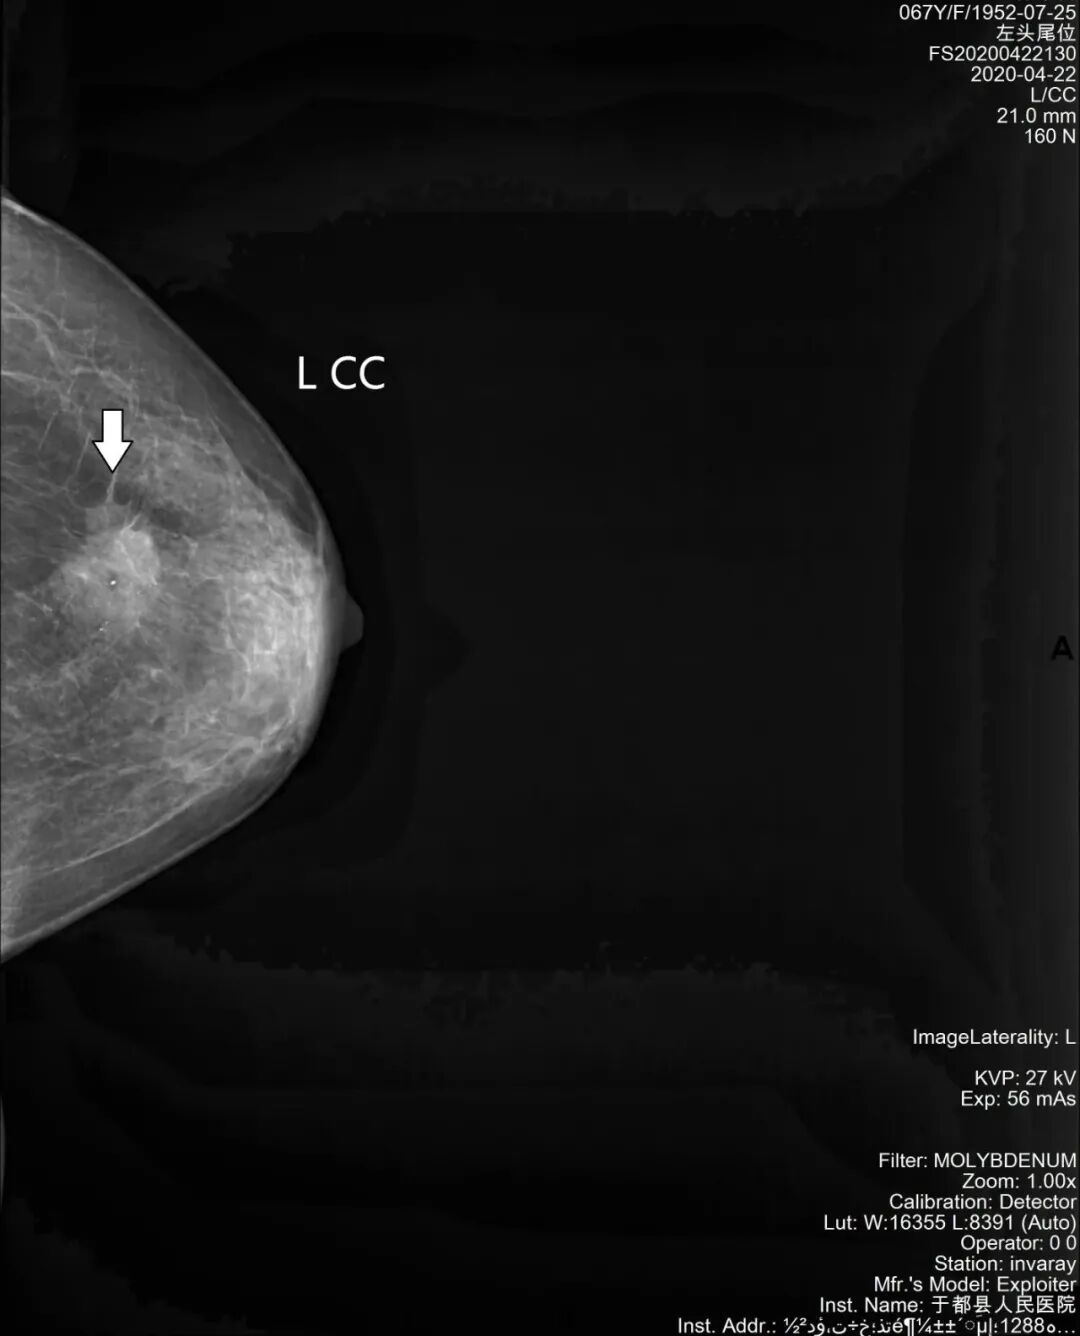

乳腺钼靶片:乳腺肿块、钙化

乳腺钼靶片:乳腺恶性钙化